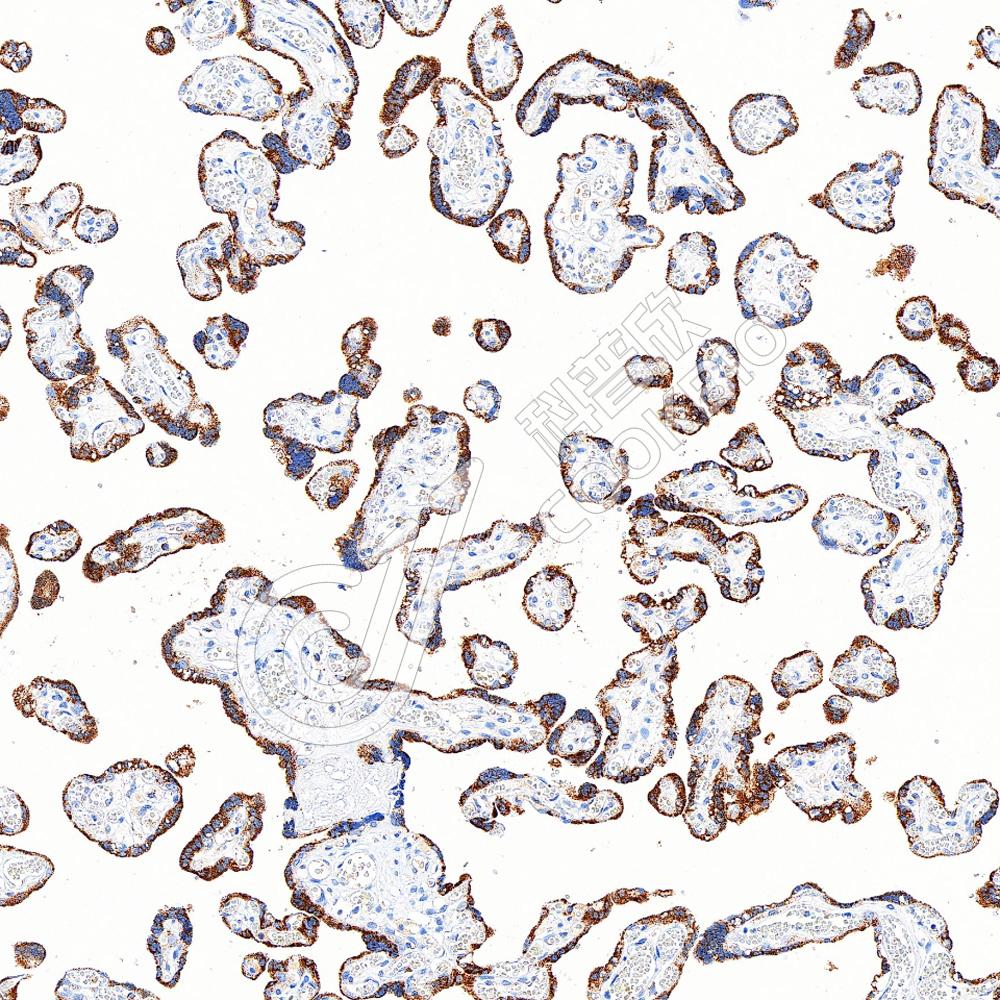

IHC检测ADX蛋白(货号 K5450273).

样品: 人胎盘, 4%多聚甲醛 (货号KSG1101) 固定12-24小时.

抗原修复: Tris-EDTA抗原修复液(pH 9.0) (KSG1203), 100℃, 25分钟.

—抗: 1: 3000稀释, 4℃ 孵育过夜.

二抗: S-vision免疫组化多聚二抗(山羊抗兔),即用型 (货号KB3906), 室温孵育20分钟.